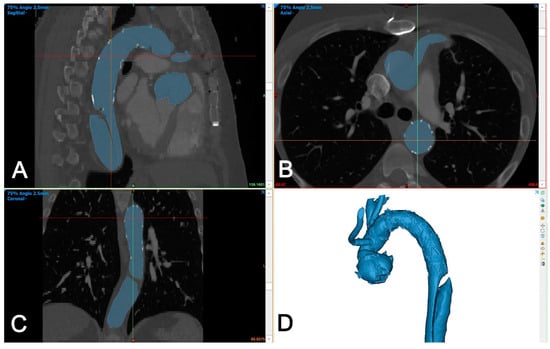

The DICOM dataset was segmented using Mimics Medical version 25 (Mimics Innovation Suite, Materialise, Belgium). The segmentation was performed using a semi-automated (threshold) tool and then the intra-aortic blood volume was separated from the surroundings using the split mask tool (Figure 3).

Figure 3.

Segmentation of aortic volume using dedicated 3D-engineering software (Mimis Innovation suite, Materialise, Belgium). (A–C): Aortic volume is semi-automatically segmented (blue color) and manually corrected in three perpendicular planes (sagittal (A), axial (B), and coronal (C)), if needed. (D): A 3D-volume is generated automatically and is used for further processing.